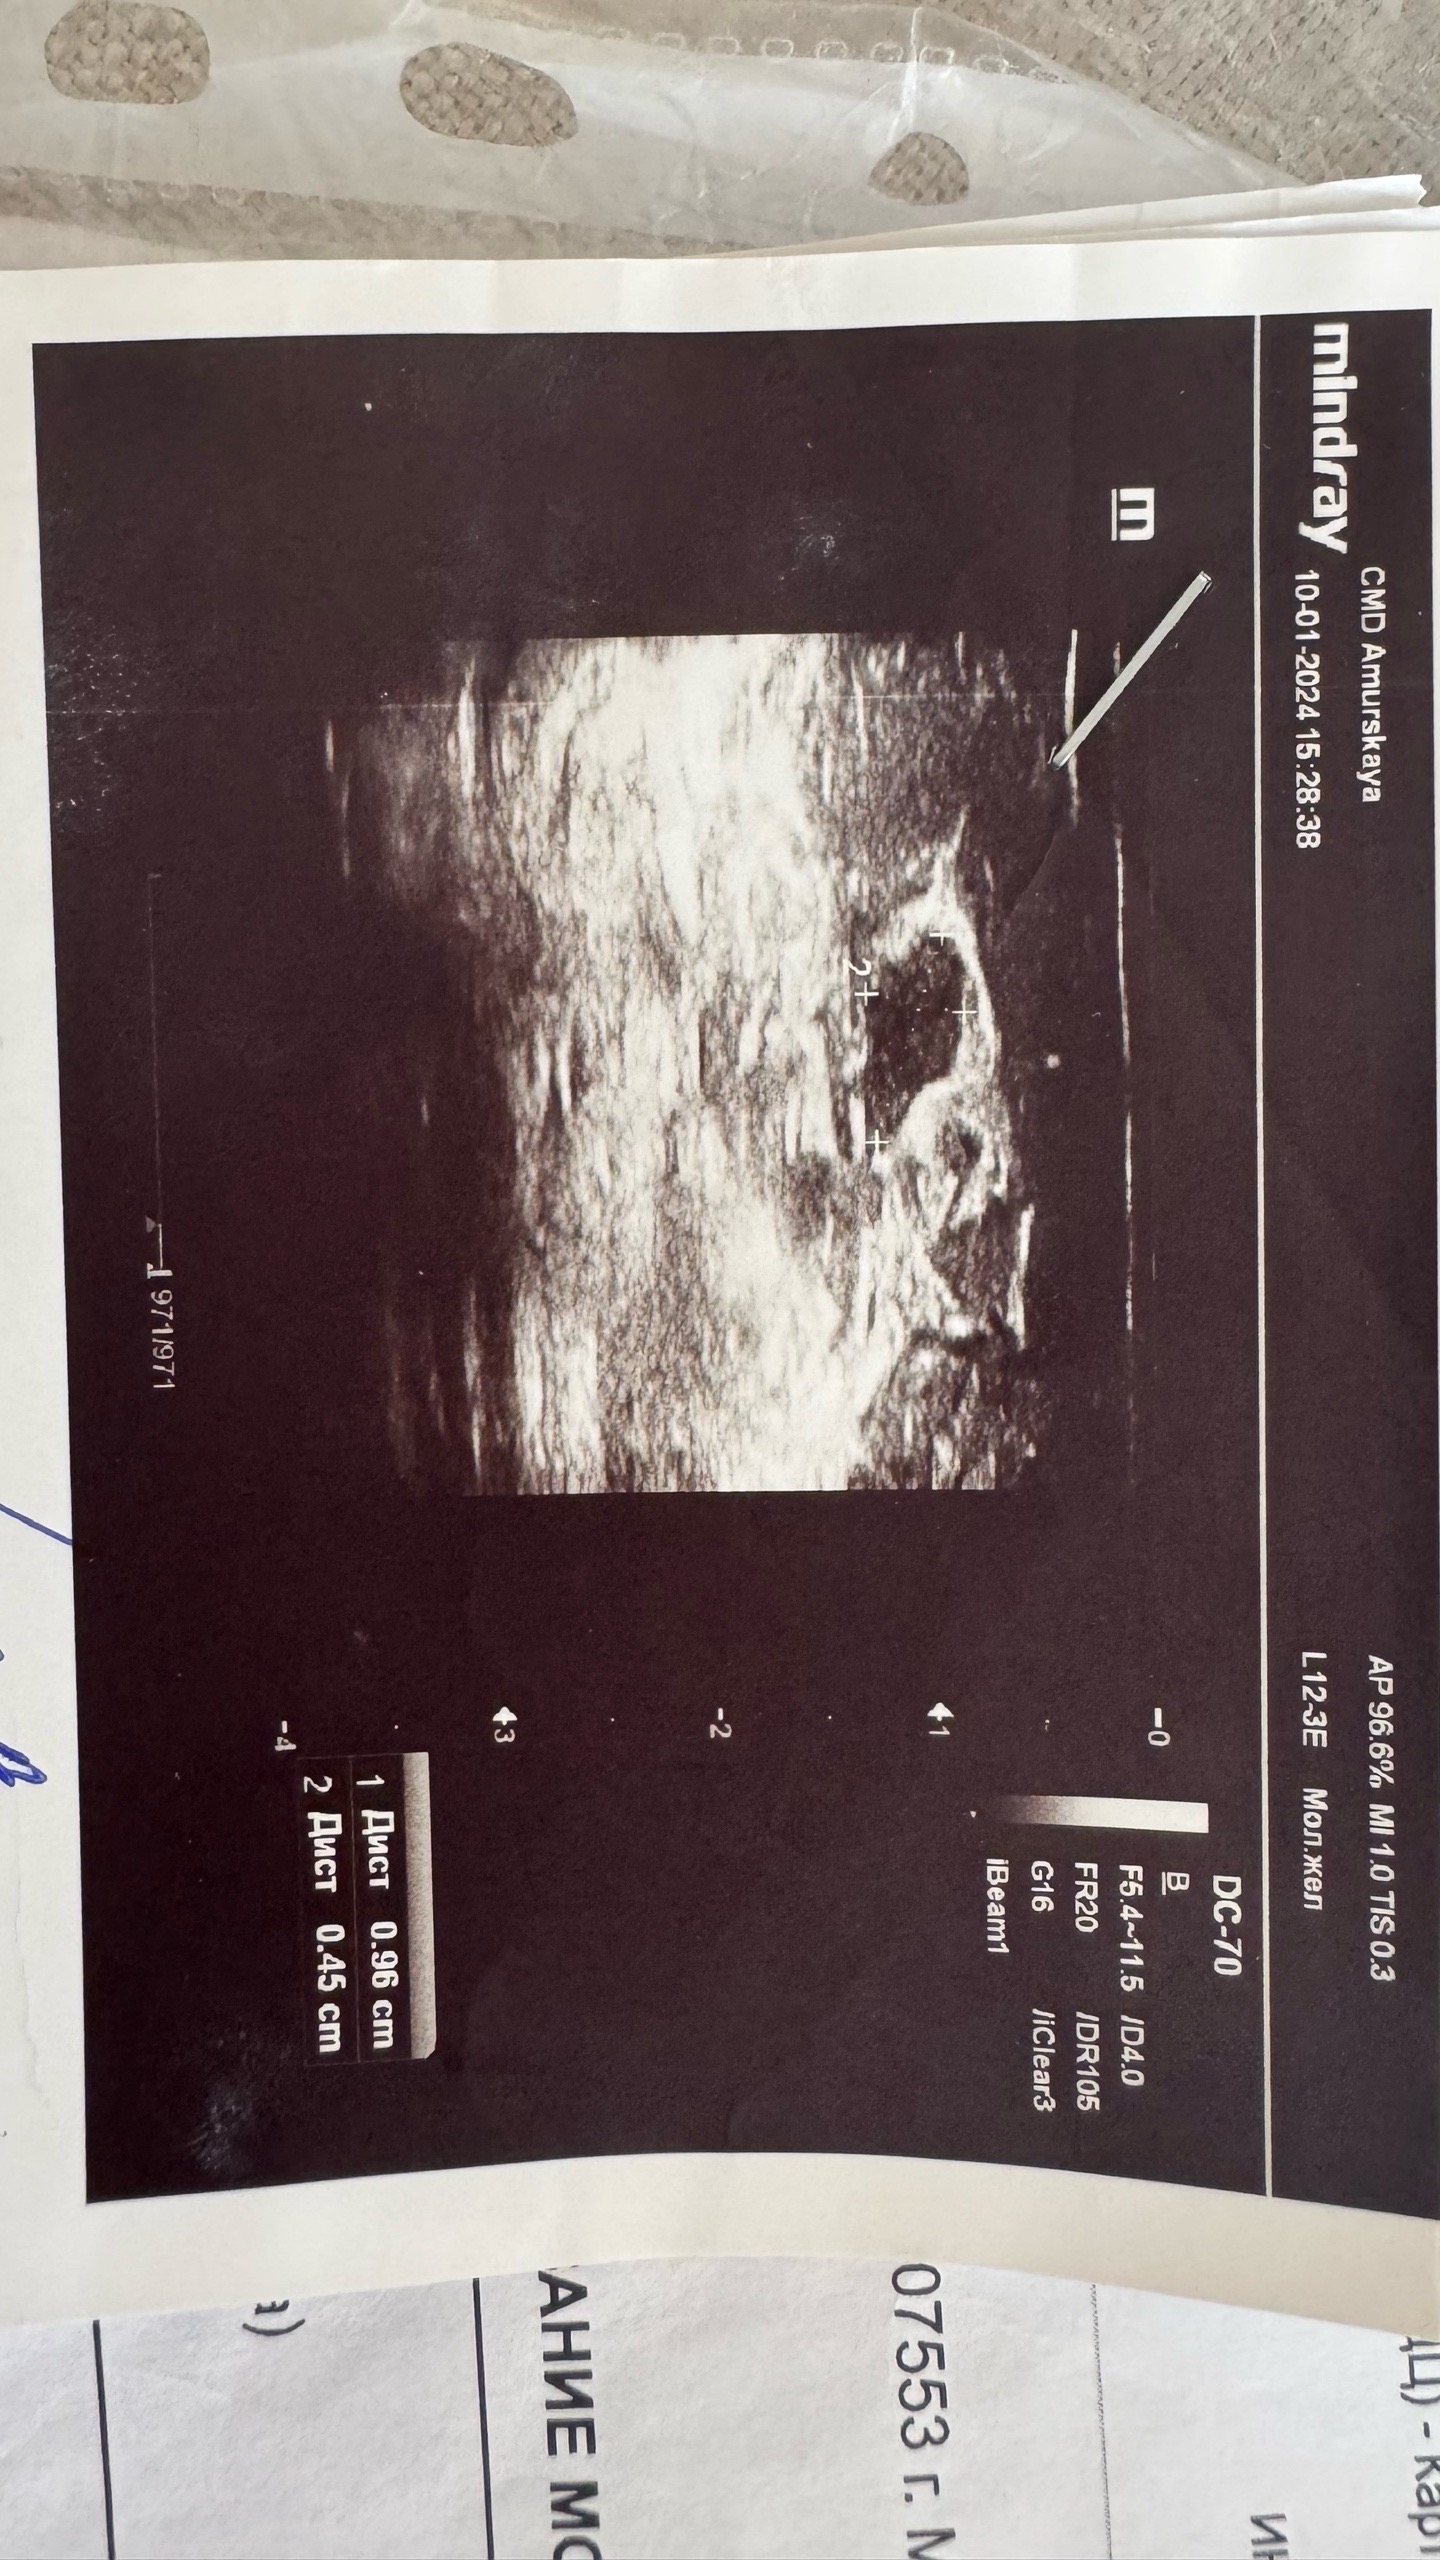

Январь 2024. В 2024 году (мне было 32) вновь пошла на узи молочных желез и на узи обнаружилось образование в левой мж "гипоэхогенное неправильной овальной формы 9,6*4,5*9,6 с четкими неровными контурами, аваскулярное". В заключении — фиброаденома? атипичная киста? под вопросом. BIRADS не написали (тогда я еще не знала о том, что узист должен присваивать уровень по этой классификации).